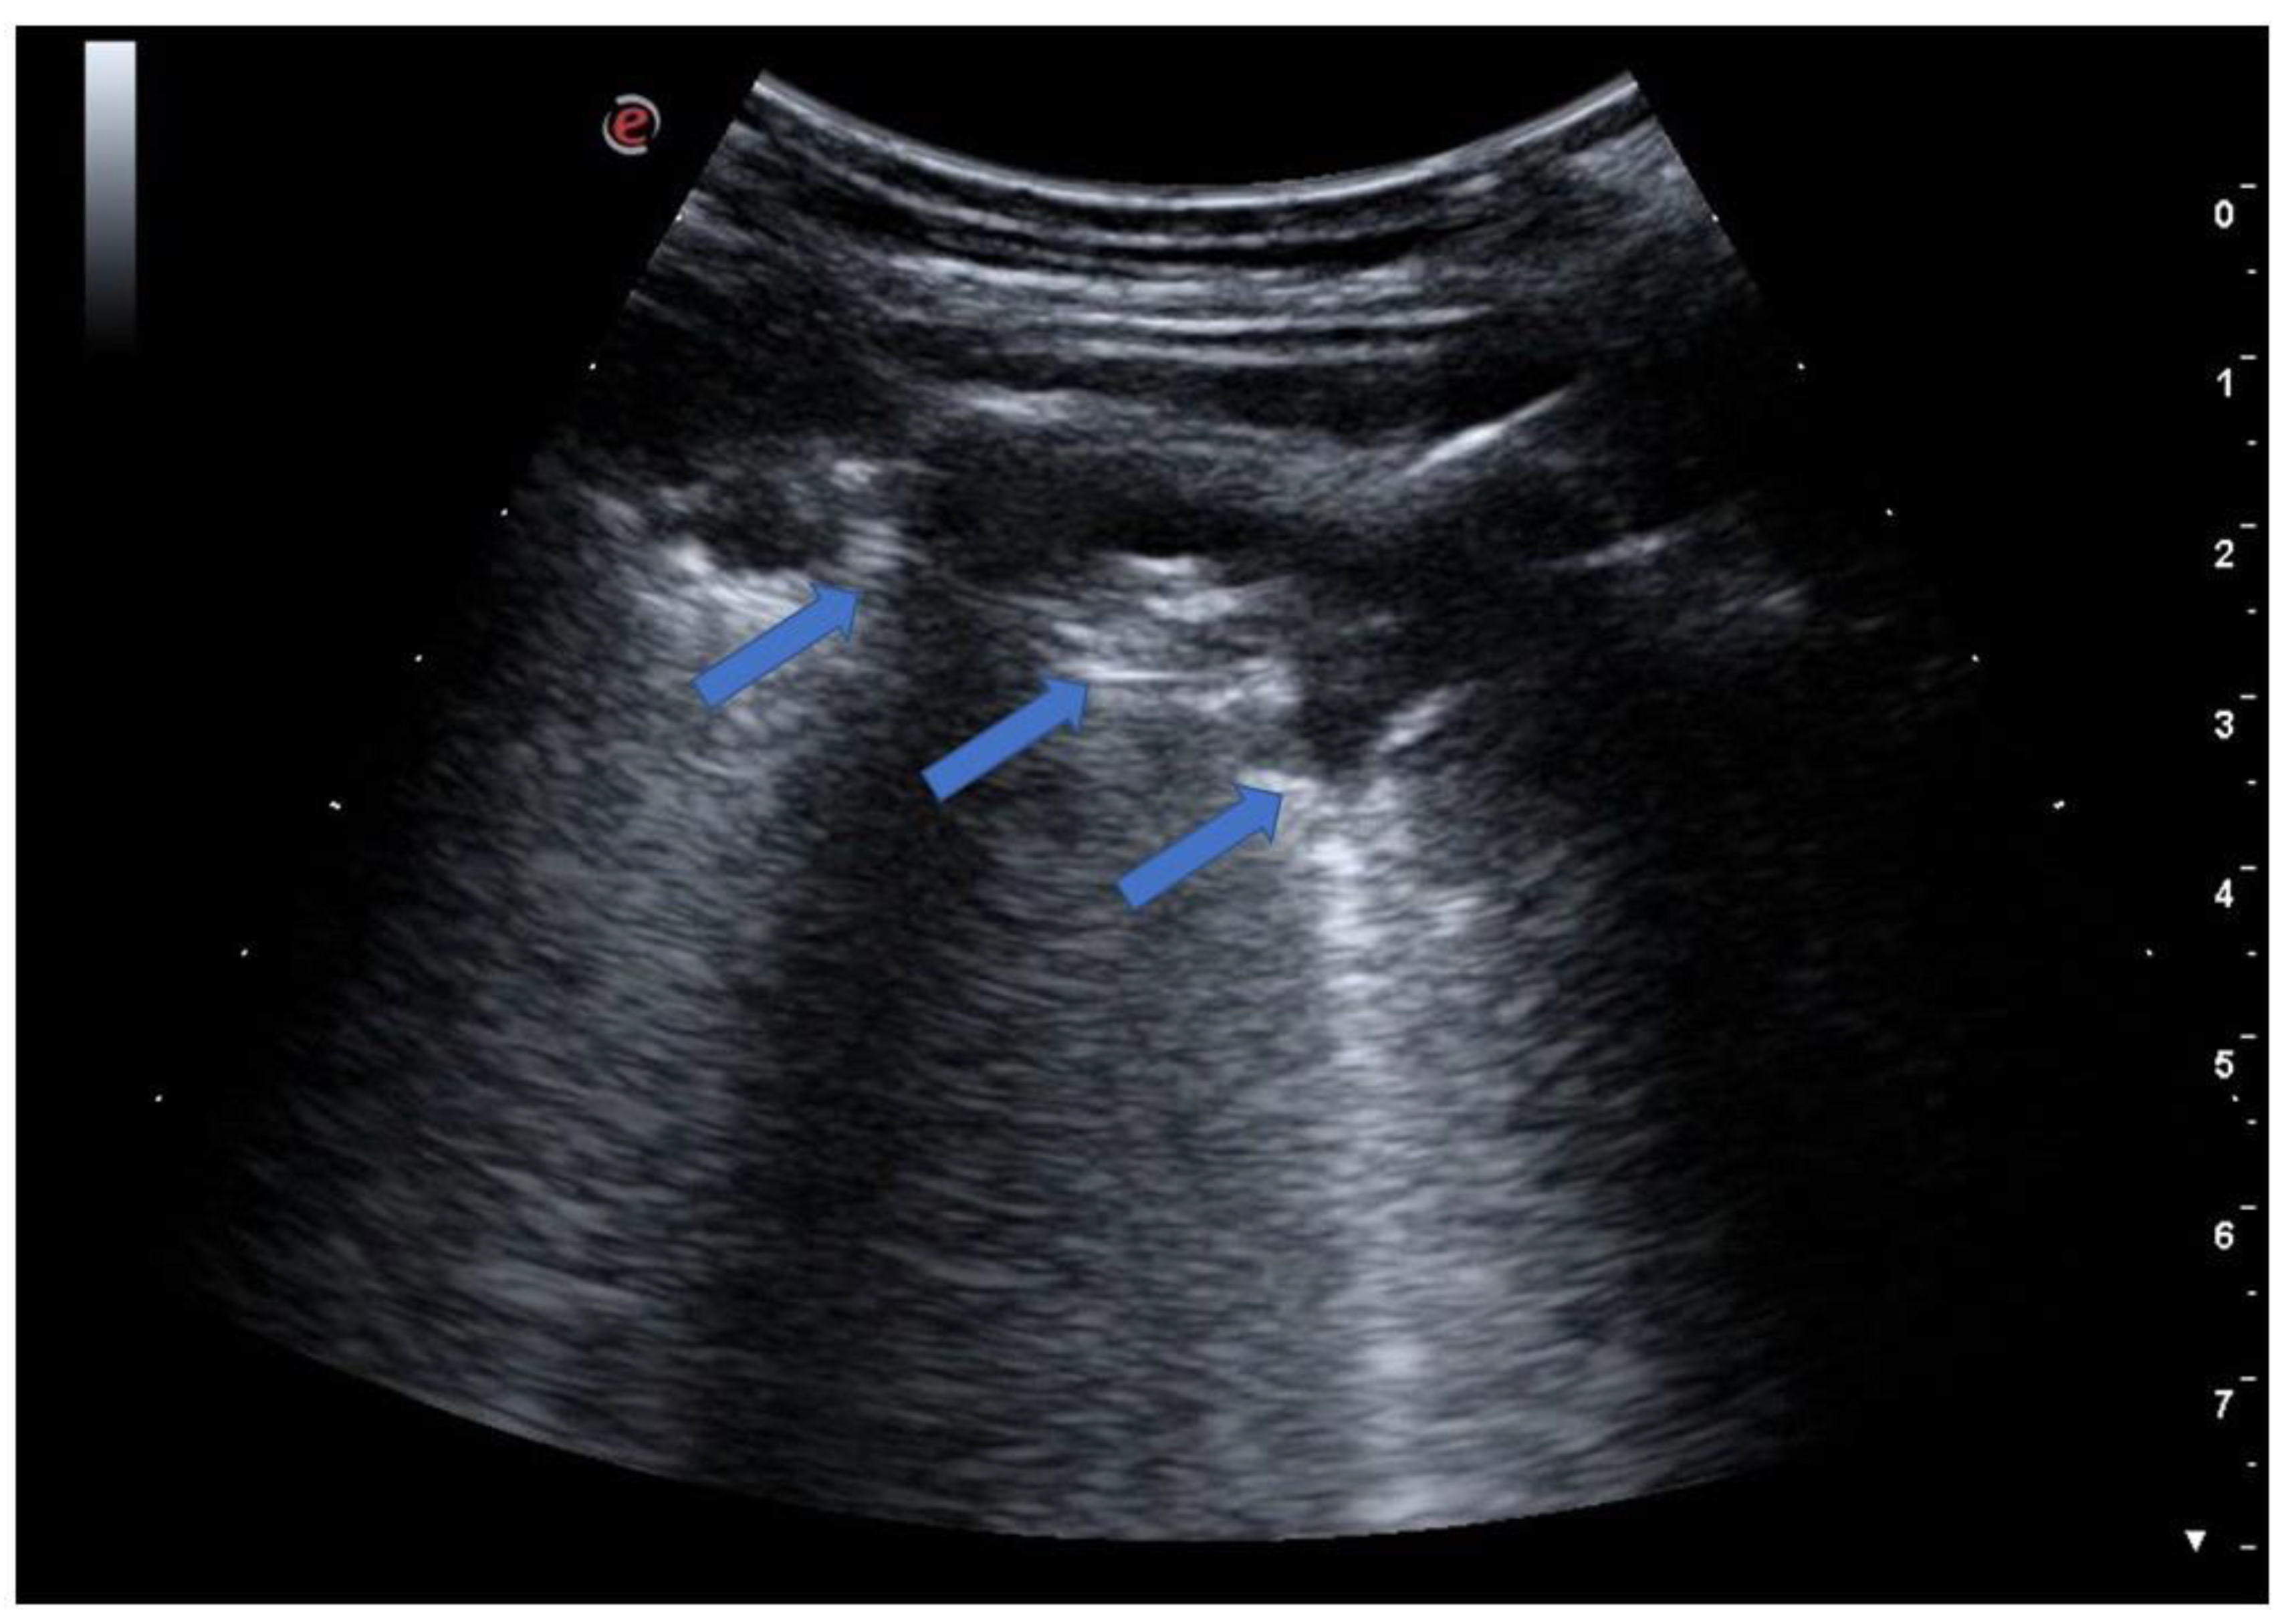

5.2. Lung Consolidations